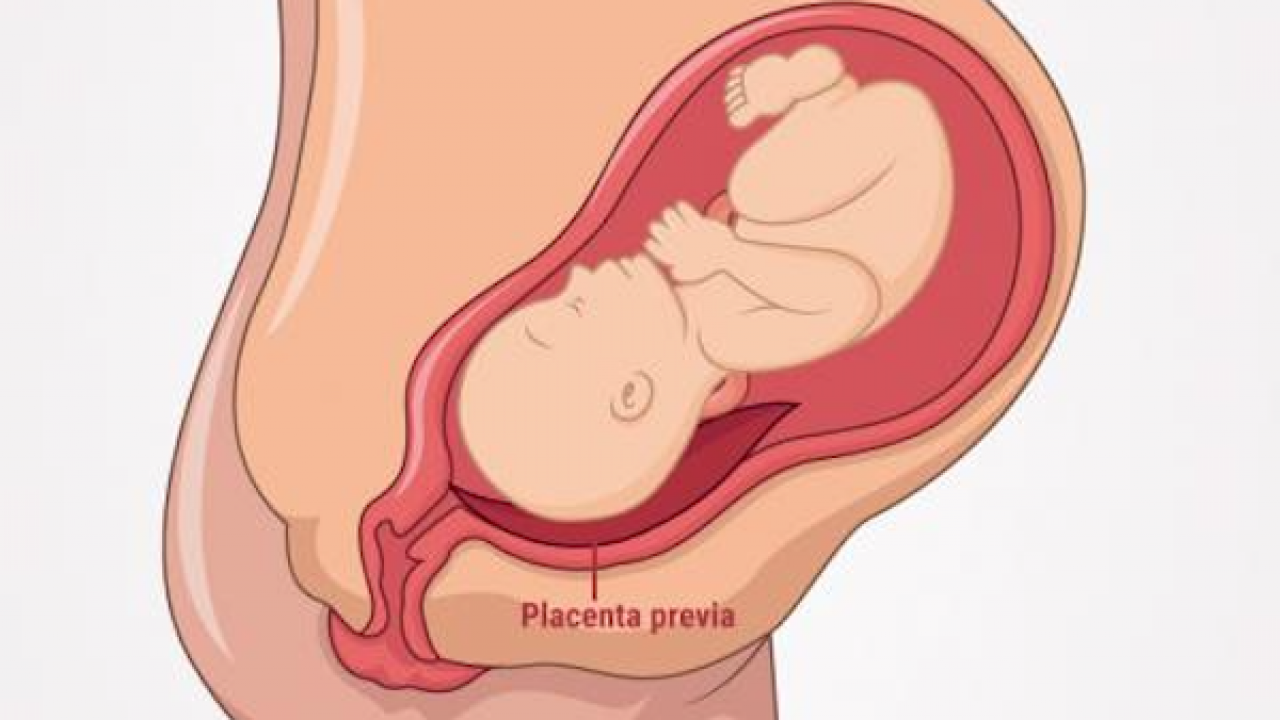

Plasenta Previa, Apa Harus Ibu Hamil Lakukan? Halaman 1 …

Plasenta Previa, Apa Harus Ibu Hamil Lakukan? Halaman 1 …

Rifky Balwel Panik Istri Pendarahan Karena Plasenta Previa …

Rifky Balwel Panik Istri Pendarahan Karena Plasenta Previa …

Plasenta Previa, Apa Harus Ibu Hamil Lakukan? Halaman 1 …

Plasenta Previa, Apa Harus Ibu Hamil Lakukan? Halaman 1 …

Placenta Previa - Bidan Kita

Placenta Previa - Bidan Kita